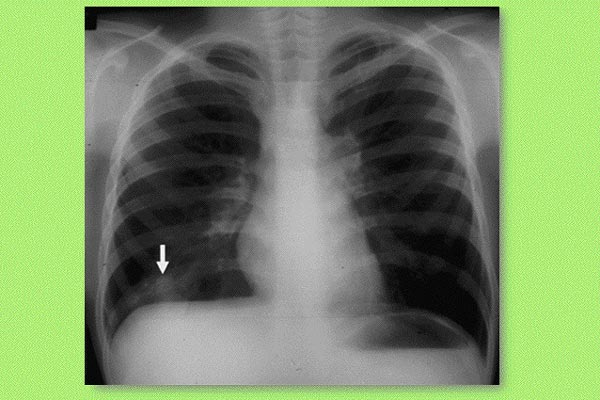

Röntgenbild